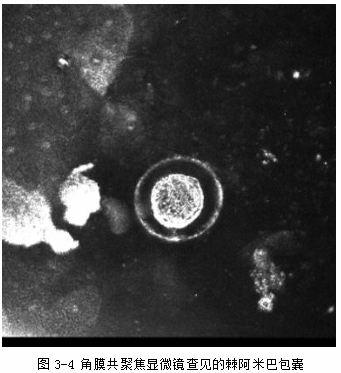

(1)角膜刮片:未找到细菌及真菌菌丝, 见棘阿米巴包囊(图3-3)。

(2)角膜共聚焦显微镜检查:见棘阿米巴包囊(图3-4)。

(5)角膜刮片、角膜共聚焦显微镜检查发现棘阿米巴包囊。